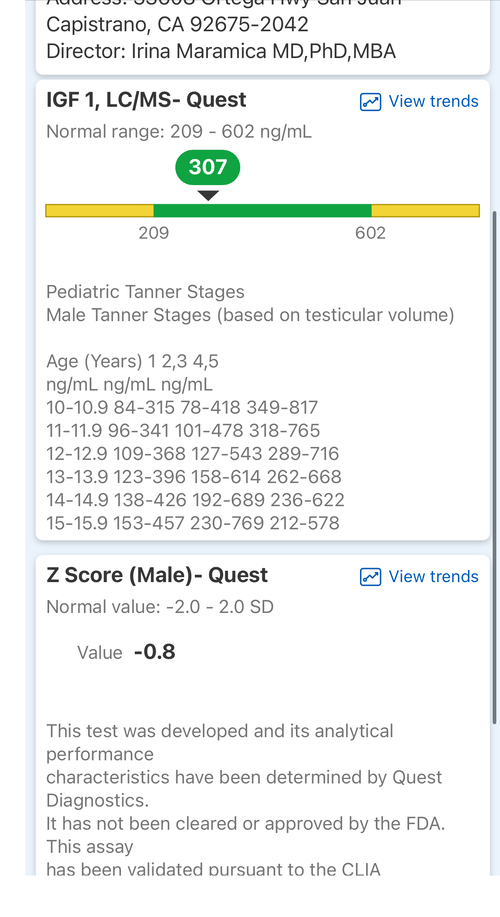

Introduction: The goal of this protocol is to hit my genetic potential. This is my first time experimenting with any pharmaceuticals. I am considering this based on my genetic potential allowing for more growth and the fact I need to take quick action if I want to hit my genetic target before my growth plates fuse. I may use an aromatase inhibitor but considering the fact my prior experience with pharmaceuticals is none I am fearful of having a “stack” of drugs and not having the resources to operate it well. I want to gain significant height in the most simple and low risk way possible. I will attach some blood work on my IGF-1, Cortisol, Testosterone and I have a bone age X-Ray which indicates my plates are open but estrogen exposure is starting the closure process. I will also attach a growth chart.

Introduction: The goal of this protocol is to hit my genetic potential. This is my first time experimenting with any pharmaceuticals. I am considering this based on my genetic potential allowing for more growth and the fact I need to take quick action if I want to hit my genetic target before my growth plates fuse. I may use an aromatase inhibitor but considering the fact my prior experience with pharmaceuticals is none I am fearful of having a “stack” of drugs and not having the resources to operate it well. I want to gain significant height in the most simple and low risk way possible. I will attach some blood work on my IGF-1, Cortisol, Testosterone and I have a bone age X-Ray which indicates my plates are open but estrogen exposure is starting the closure process. I will also attach a growth chart.